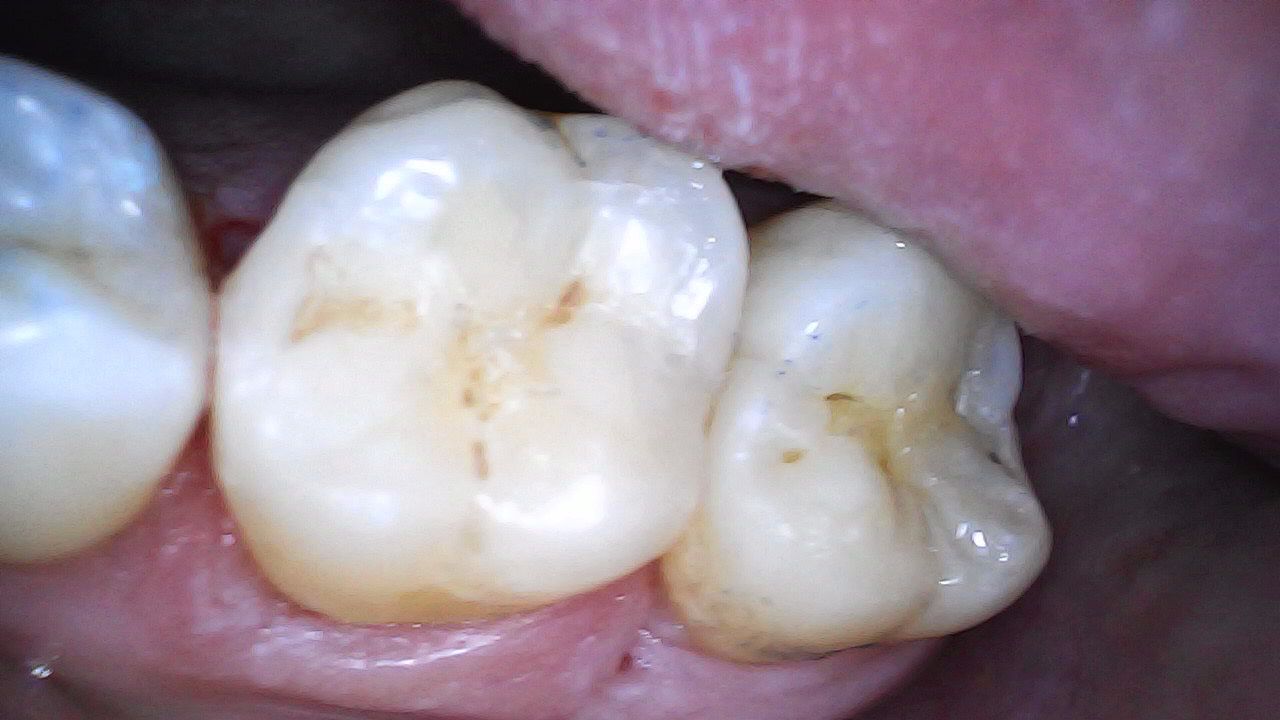

6 months post-op - Is still vital